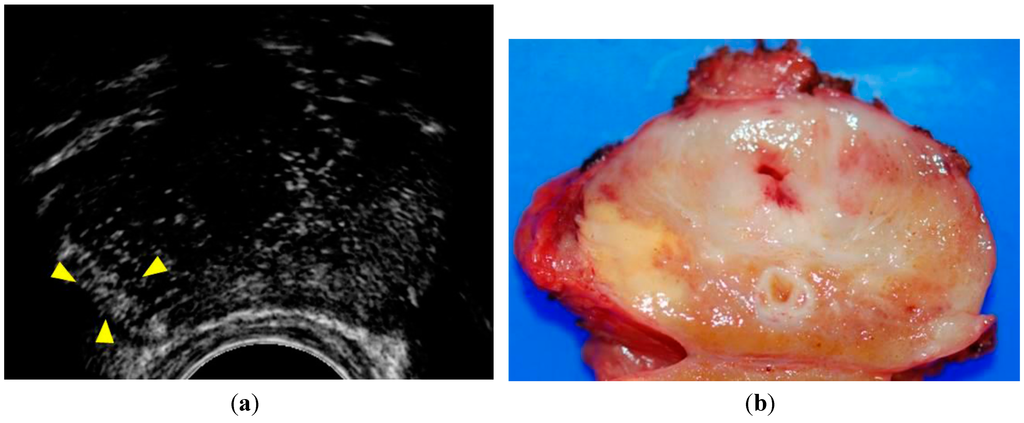

- Sano, F.; Terao, H.; Kawahara, T.; Miyoshi, Y.; Sasaki, T.; Noguchi, K.; Kubota, Y.; Uemura, H. Contrast-enhanced ultrasonography of the prostate: Various imaging findings that indicate prostate cancer. BJU Int. 2011, 107, 1404–1410. [Google Scholar] [CrossRef] [PubMed]